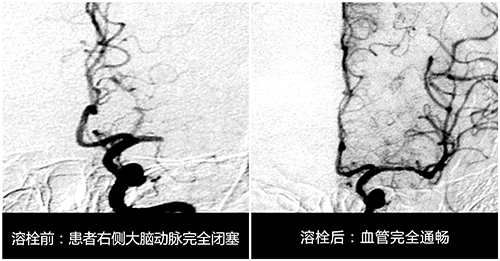

孫主任對急性腦梗死溶栓治療進行了深入的研究,也是當時國內(nèi)率先開展溶栓研究最早的專家之一。自1995年NINDS研究以后,美國、歐洲、加拿大等國將溶栓治療超急性期缺血性卒中納入腦血管病治療指南,這種方法大大提高了梗死患者治療的有效性及預后,這鼓舞著孫曉江朝著這個方向繼續(xù)研究,他也多次參加國際神內(nèi)學會會議,以擷取先進的理念和方法。

為了更好的進行研究他建立了自己的早期團隊,是由他所帶的研究生組成。據(jù)孫主任介紹,進行溶栓研究的要求是非常嚴格的,從溶栓治療患者的選擇,到治療后并發(fā)癥的預防,再到溶栓治療的評估,以及影像學診斷與療效評估,他都建立了一整套體系標準,并要求學生嚴格按照標準執(zhí)行,其中最重要的一點是盡可能在“4.5黃金時間窗”內(nèi)進行溶栓治療。

1996年11月某天,65歲的張阿姨突發(fā)腦梗死,來院時張阿姨腦梗死已病發(fā)3—4小時。“當時患者腦梗死情況還是比較嚴重的,雖然她的意識還算清醒,但右側肢體已經(jīng)偏癱,上肢和下肢的肢體肌力評分幾乎為零級,手腳當時一點也不能動,如果不及時進行有效救治,患者不僅會右側身體偏癱,還可能會危及生命。”孫主任介紹說。

面對如此緊急的時刻,孫主任第一時間安排患者進行相關檢查,隨后根據(jù)患者的病癥及檢查結果進行了嚴格的評估,確定患者符合靜脈溶栓的要求。緊接著對患者進行溶栓治療,經(jīng)過半小時的精心溶栓后,患者的肢體竟都能動了,病人和家屬當時激動得千恩萬謝。